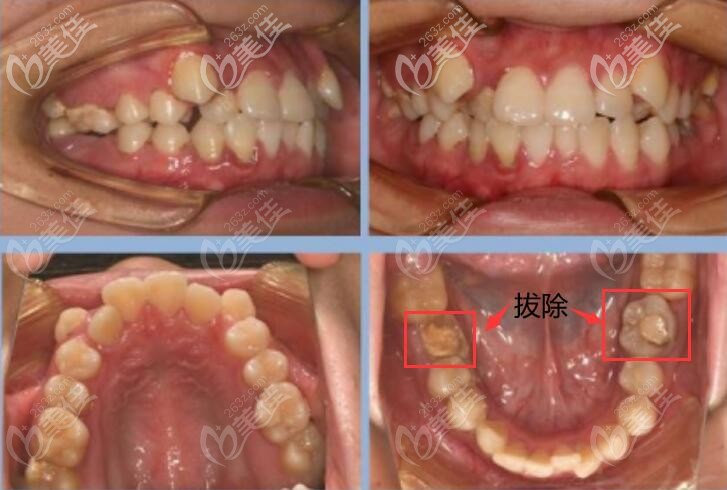

術(shù)前照片:

牙齒不整齊導(dǎo)致凸面型;也就是常說(shuō)的虎牙(又叫尖牙)。

拔除牙齒:15,25,46,36;對(duì)于萌生不正的智齒進(jìn)行正確的牽引,扶正后向前排齊。